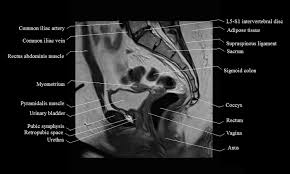

Posted by kenneth on november 18, 2019. Mri is the modality of choice in assessing the complex perineal lesions and their relations to the adjacent structures. 6.1a, b) is a bony ring consisting of paired innominate bones, the sacrum and coccyx. Anatomically, the pelvis can be divided into true and false pelvis by an oblique line that extends from the sacral promontory along the anterior aspect of s1 to the symphysis pubis. Pelvic muscle anatomy chart, pelvic muscle anatomy male, pelvic muscle anatomy pdf, pelvic muscles anatomy axial, pelvic muscular anatomy ct, human muscles, pelvic muscle anatomy chart, pelvic muscle anatomy male, pelvic muscle anatomy pdf, pelvic muscles anatomy axial, pelvic muscular anatomy ct. Magnetic resonance imaging (mri) devices can provide direct transverse, sagittal, and coronal plane images. If these muscular tissues end up being weak. Wasnik, mbbs, mda, michael b. Use the mouse scroll wheel to move the images up and down alternatively use the tiny arrows (>>) on both side of the image to move the images.>>) on both side of the image to move the images. Mri anatomy images of the abdomen. Dotted line in a ) show the anatomy of the. The innominate bones articulate with each other anteriorly and with the sacrum posteriorly. The majority of the time, these muscular tissues are quite solid and also are able to support the pelvic bone.

This mri male pelvis axial cross sectional anatomy tool is absolutely free to use. Use the mouse scroll wheel to move the images up and down alternatively use the tiny arrows (>>) on both side of the image to move the images.>>) on both side of the image to move the images. Anteriorly, pubocervical fibromuscularis is attached to the levator ani using arcus tendineus fascia pelvis (fig. The majority of the time, these muscular tissues are quite solid and also are able to support the pelvic bone. Anatomically, the pelvis can be divided into true and false pelvis by an oblique line that extends from the sacral promontory along the anterior aspect of s1 to the symphysis pubis. Pelvic bones are held together by the two main joints of the pelvis; This mri hip joint axial cross sectional anatomy tool is absolutely free to use. The pelvic cavity opens superiorly to, and is continuous with, the abdominal cavity through the pelvic inlet. 1 the greater, or false, pelvis is situated above this plane. E anatomy is an award winning interactive atlas of human anatomy. In this image, you will find ascending colon, appendix, psoas muscle, ureter, gluteus minimus, lumbosacral trunk, gluteus medius, gluteus maximus, sacroiliac joint, the lateral sacral crest in it. This is since pelvic muscular tissues are generally one of the major weak points in a lady's body. Key facts about the muscles of the pelvic floor.

A pelvis mri (magnetic resonance imaging) scan is an imaging test that uses a machine with powerful magnets and radio waves to create pictures of the single mri images are called slices. The pubic symphysis and the sacroiliac joint, and reinforced by pelvic muscles. The bony framework of the pelvis is called the pelvic girdle.it is composed of the two hip bones and the sacrum. E anatomy is an award winning interactive atlas of human anatomy. Conclusions • the primary imaging modalities for the abdomen and pelvis are plain film, ultrasound, and ct. This mri pelvis cross sectional anatomy tool is absolutely free to use. Pelvic bones are held together by the two main joints of the pelvis; This mri hip joint axial cross sectional anatomy tool is absolutely free to use. Mri is the modality of choice in assessing the complex perineal lesions and their relations to the adjacent structures. 12 photos of the pelvic muscle anatomy mri. They form a large sheet of skeletal muscle that is thicker in some areas than in others. Although ultrasound is frequently indicated for the primary evaluation of Anatomically, the pelvis can be divided into true and false pelvis by an oblique line that extends from the sacral promontory along the anterior aspect of s1 to the symphysis pubis.